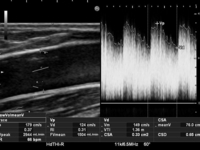

・グラフト内血流

人工血管内シャントにおいては、基本的には自己血管内シャントと同様に上腕動脈血流量での評価をおこないますが、グラフト内での血流測定が可能な場合は測定し参考にしています。※人口血管の種類によってはエコーを通さず測定できない